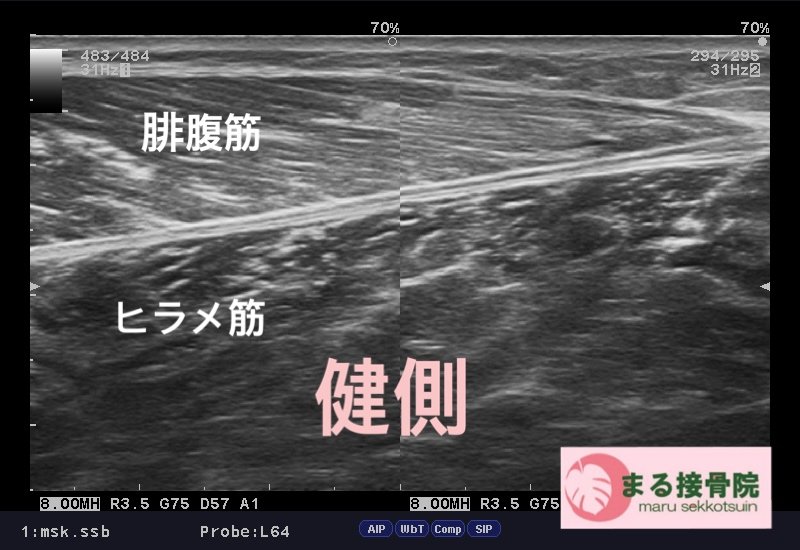

今日の患者様は、テニス中、ふくらはぎが「誰かに後ろから蹴られた、、、ような」「力を入れた時にブチッ!!と痛みがはしった、、、」と御来院。

肉離れはスポーツ中、日常生活で階段を駆け上がるなど、筋肉に急激な力が加わった時に、筋繊維が損傷した状態。

治療は、しっかり問診、触診、視診を行い、超音波画像診断装置で患部状態、深さ、広さをしっかり確認し、早期復帰、回復に向けて対処していきます。

まずは患部の出血、腫れを最小限に抑え、周囲の筋肉も硬くならないようにし、タイミングを診てストレッチ、リハビリを行って参ります。